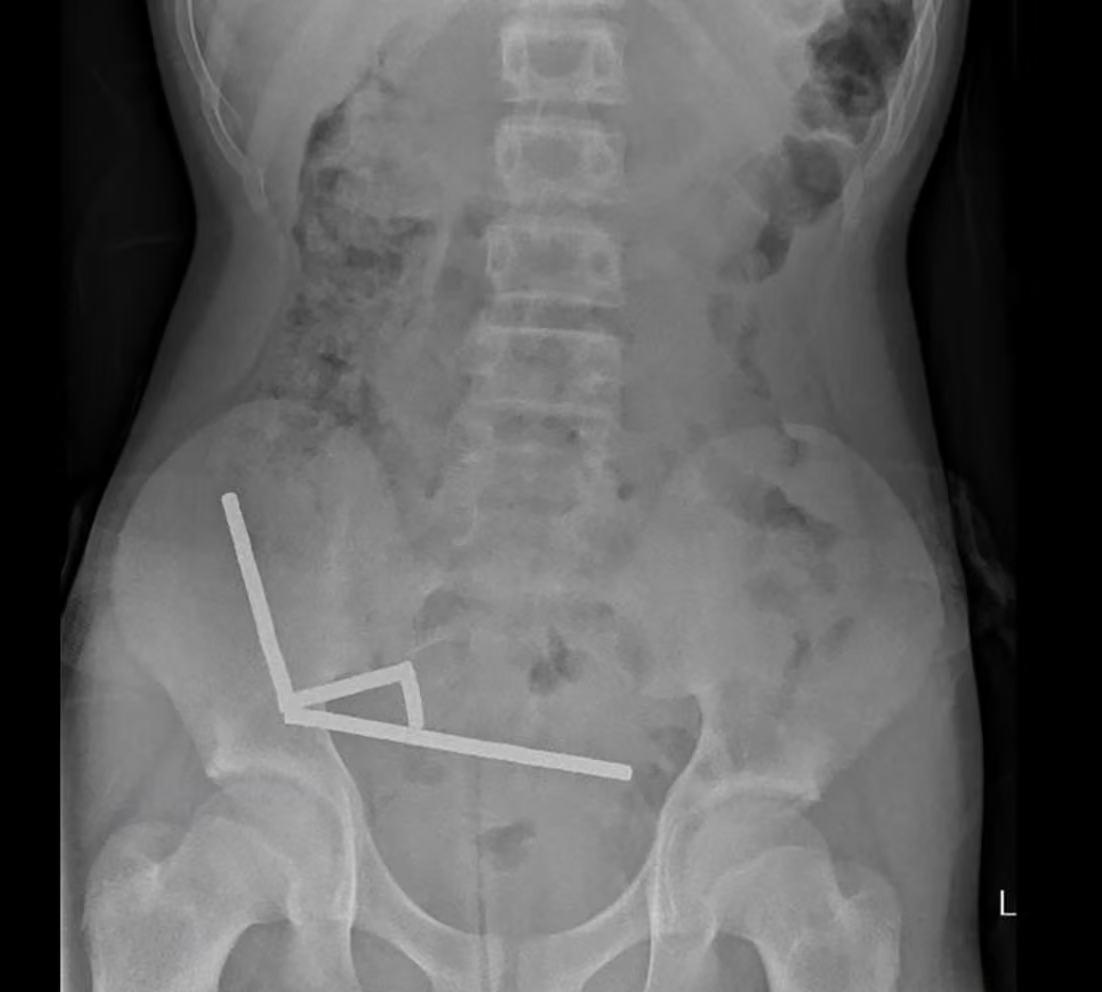

Our second story too comes from the bowels of the medical system. The setting this time is the intestinal system of a 13-year-old New Zealand boy, where roughly 100 magnets converged to create a knotty [IMG: The

x-rays, magnets all in rows] problem. Three days after ingesting 5x2 mm neodymium magnets he'd bought online, he began experiencing excruciating abdominal pain. Four days later, he arrived at Tauranga Hospital, where x-ray imaging revealed four neat lines apparently 'in separate parts of bowel [that] adhered together due to magnetic forces'. He spent eight days in hospital once surgeons had removed both the magnets and the portions of the organ where their pressure had led to necrosis.